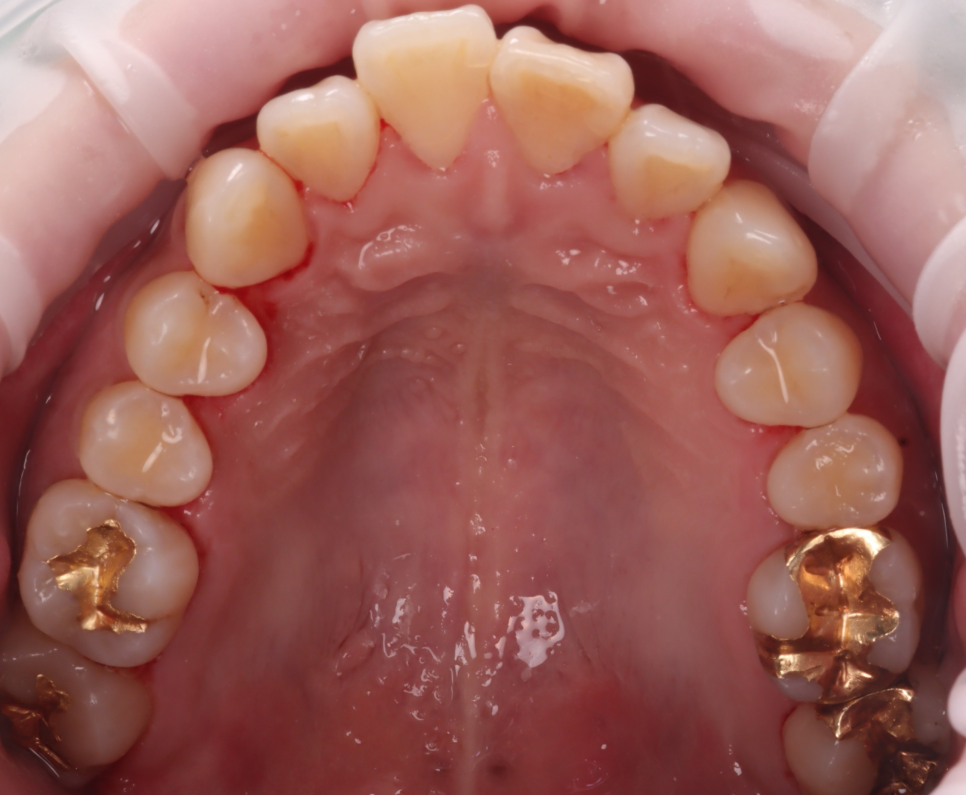

하지만 에어플로우로 착색을 제거하고 나니

치아 본연의 색이 드러났고

전체적으로 아주 깔끔해졌습니다.

촬영일 : 250607